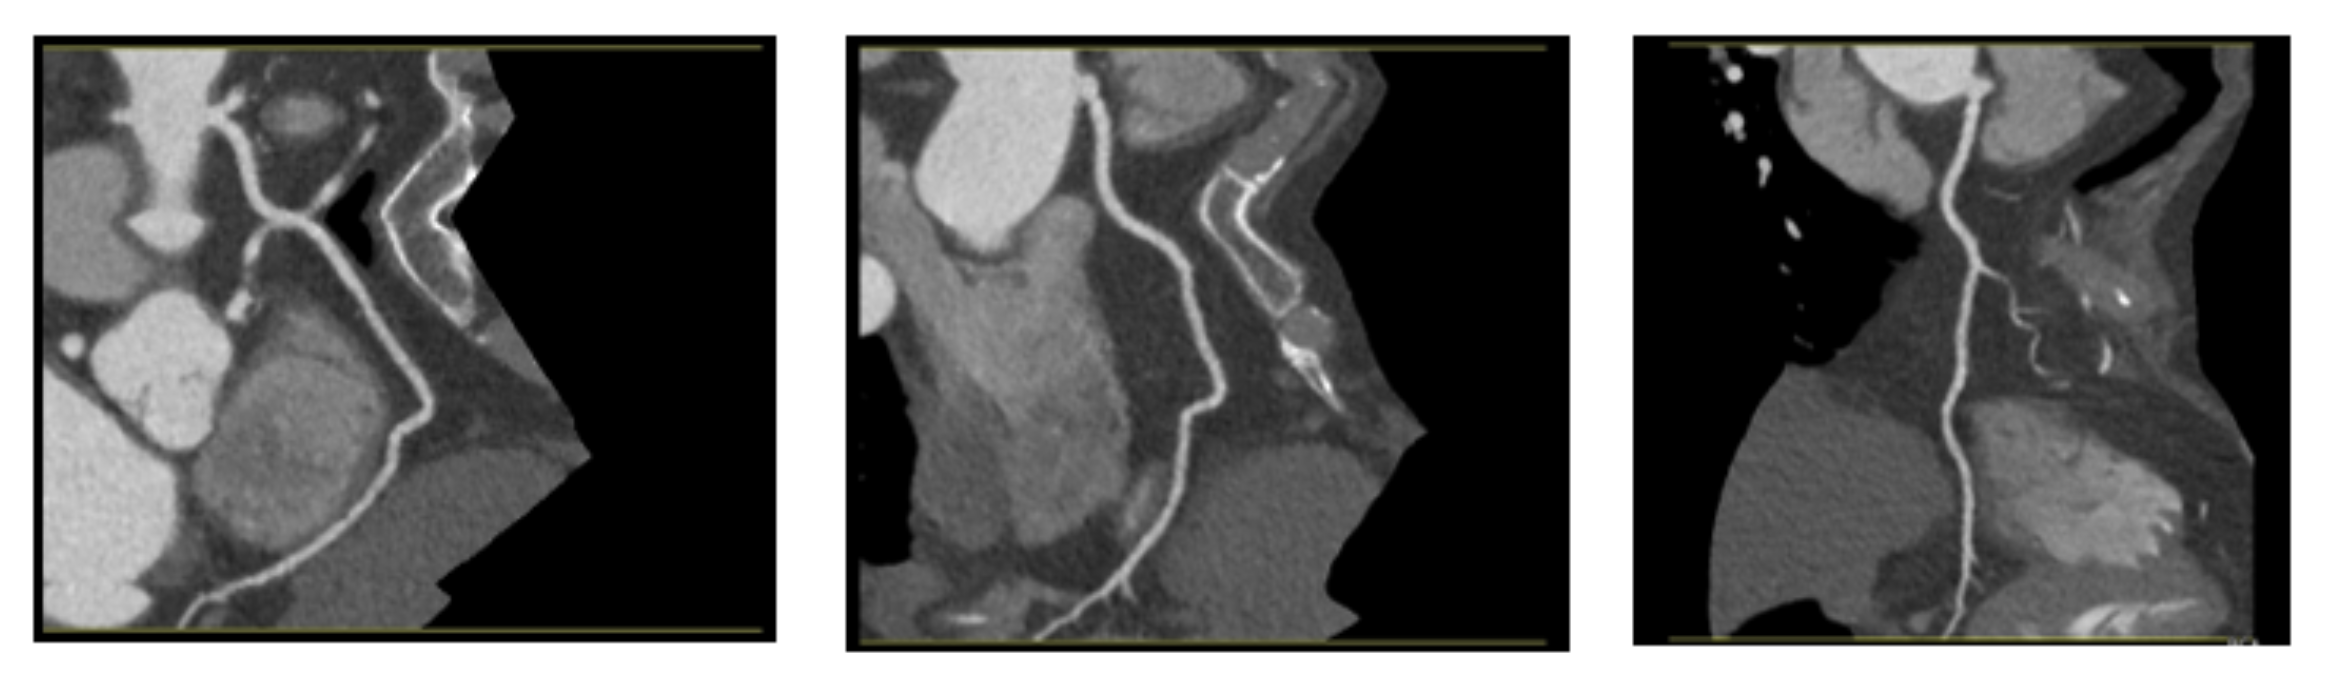

3.1. Dataset

3.1.1. Dataset Composition